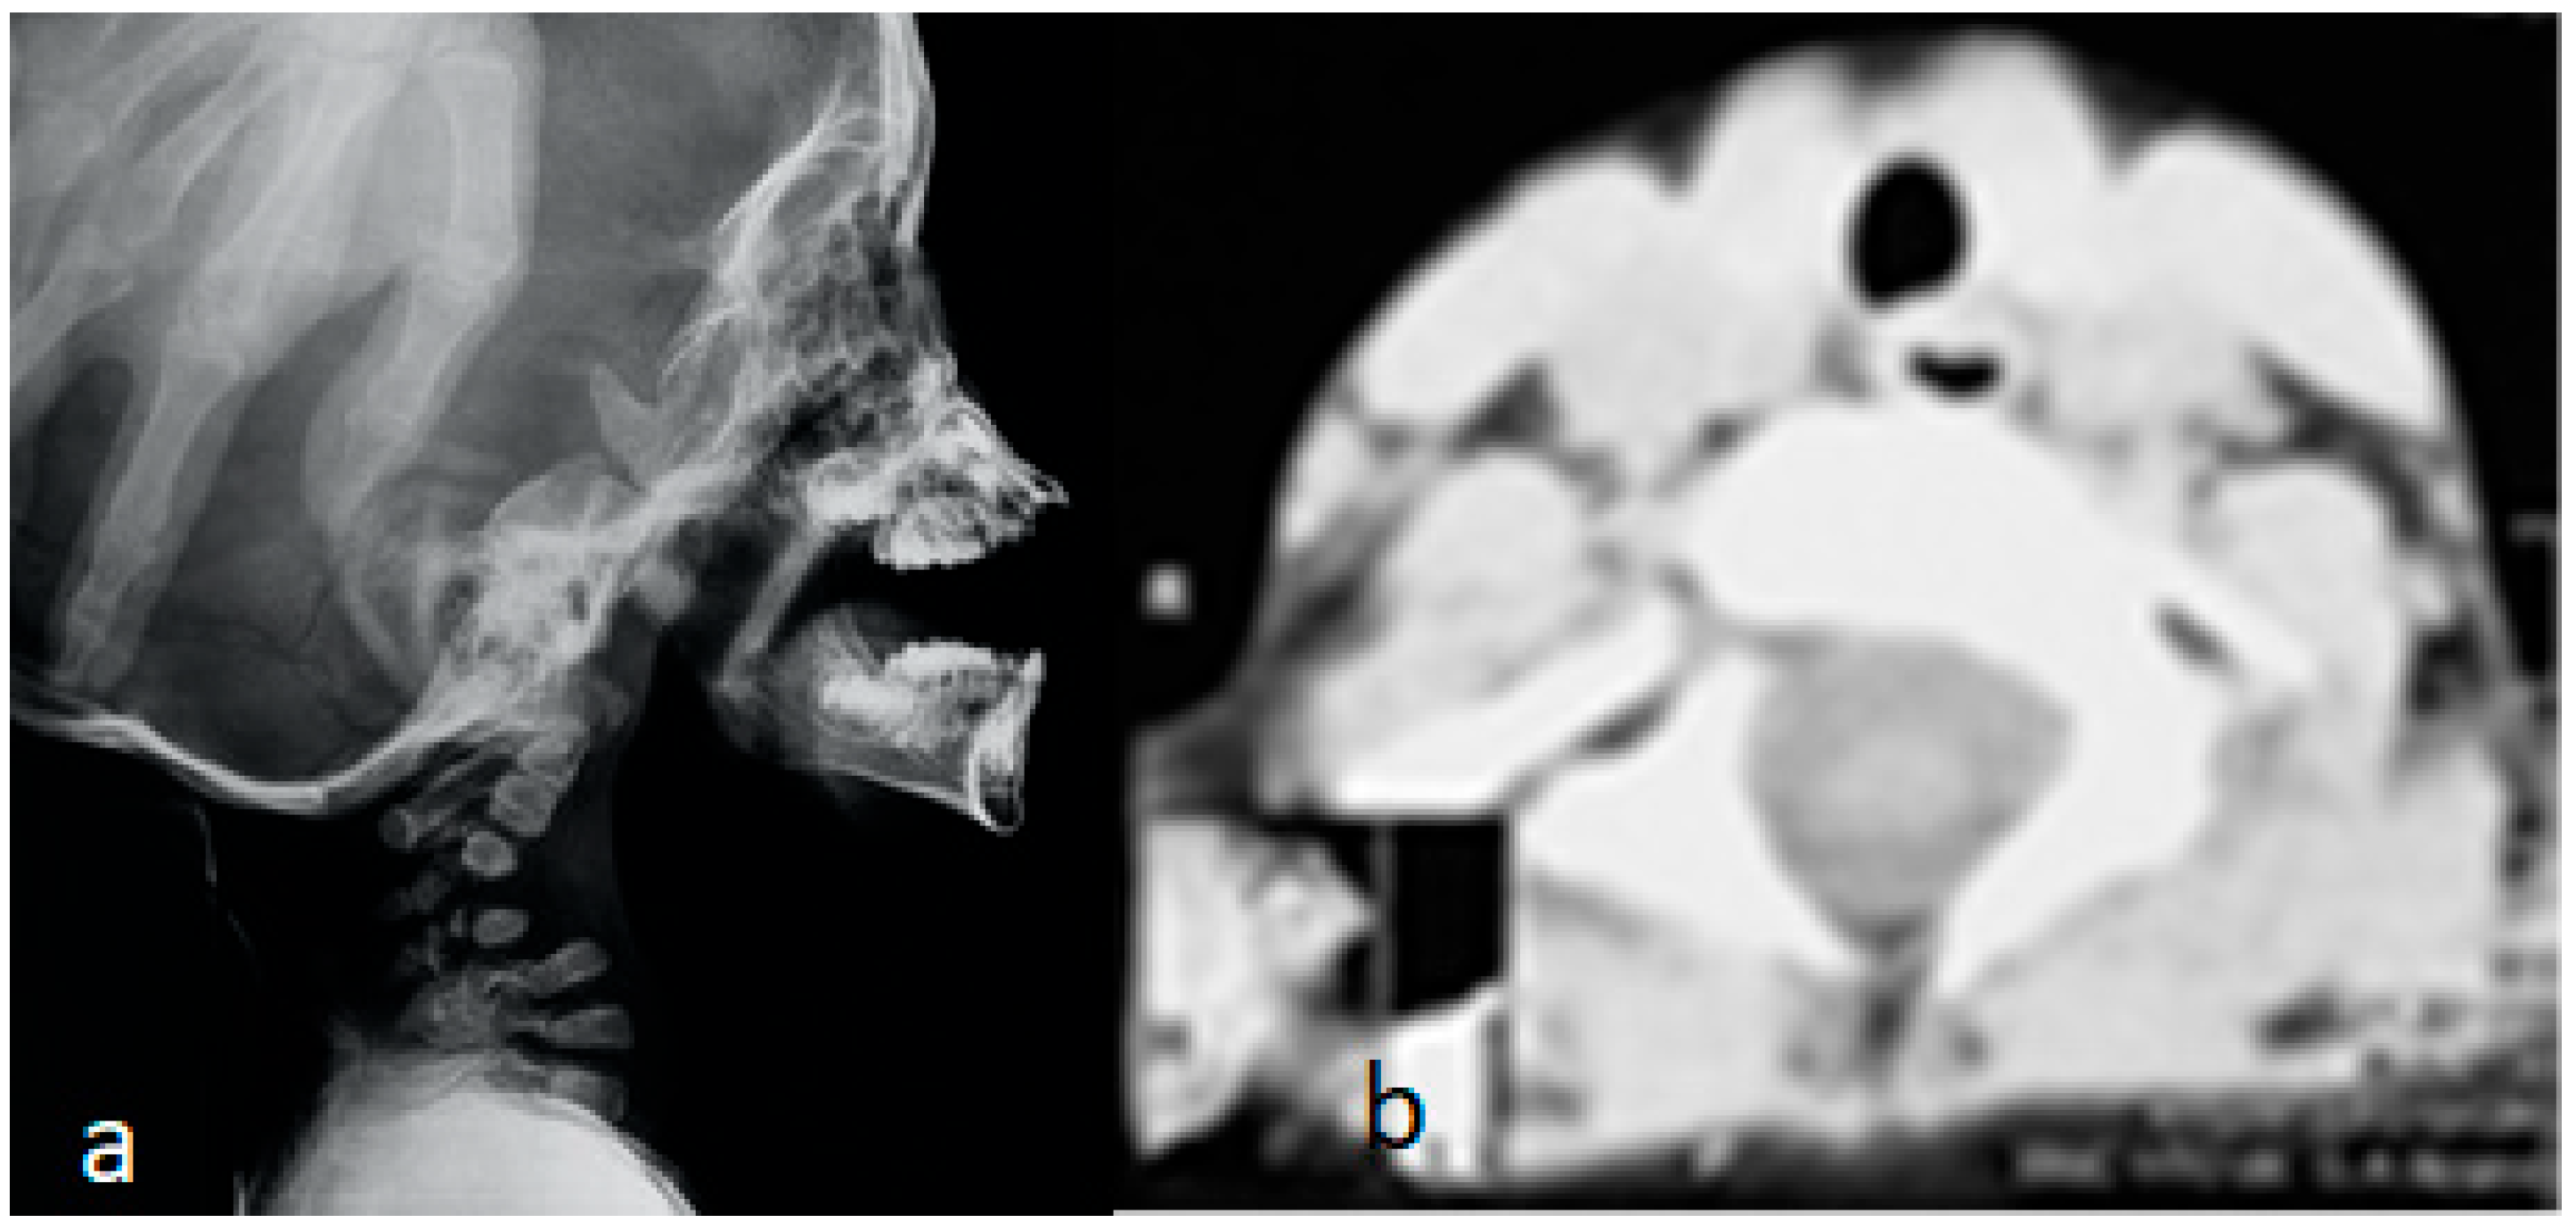

In these children, dysmorphic facial features were evident, which encompassed distinctive facial features, frontal bossing, and a flattened nasal bridge giving the facial phenotype of a dish-like facies. Our orthopedic strategy is based upon detailed clinical and radiological phenotypic characterization. Radiological phenotypic interpretations have been organized for all children by referring to 3D CT scan. In a lateral skull radiograph of a 7-month-old boy with Larsen syndrome, one can note brachycephaly, frontal bossing, and marked disproportionate small facial bones in comparison with a large cranium and dysplastic cervical spine, osteopenia of the lambdoid bones causing downward bulging, and prominence of the occipital bone associated with progressive thinning of the squamous part of the occipital bone (arrow). One can also note the cervical kyphosis (arrow) AP hand radiograph of a 3-year-old boy with Larsen syndrome showing retarded bone age, expansion of the distal ends of the shortened metacarpals, a thumb proximally placed, and the presence of accessory bone adjacent to the distal third metacarpal-phalangeal bone (arrow). One can also see the delta phalanx of the middle metacarpophalangeal bone of the fifth finger (arrow) (b) (Figure 1a,b). The AP pelvis radiograph of a 7-month-old girl with Larsen syndrome showed bilateral hip dislocation associated with maldevelopment of a severely dysplastic acetabulum and dysplastic capital femoral epiphysis (a). The AP pelvis radiograph of a 3-year-old boy with Larsen syndrome showed bilateral hip dislocations (severe acetabulo-femoral dysplasia) (Figure 2a). The AP pelvis radiograph of a 7-month-old girl with Larsen syndrome showed bilateral hip dislocation associated with maldevelopment of a severely dysplastic acetabulum and dysplastic capital femoral epiphysis (a). The AP pelvis radiograph of a 3-year-old boy with Larsen syndrome showed bilateral hip dislocations (severe acetabulo-femoral dysplasia) (Figure 2b). AP knees radiograph of a 5-month-old boy with Larsen syndrome showing bilateral knee dislocations (arrows) associated with under tubulation of the tibae and fibulae. Note the fragmented/deformed epiphyses and that the right tibia is medially subluxated. Note bilateral talipes equinivarus associated with double ossifications of the calcaneus (arrows) (Figure 3).

Figure 1.

(a,b): Lateral skull radiograph of a 7-month-old boy with Larsen syndrome. Note brachycephaly, frontal bossing, and marked disproportionate small facial bones in comparison with a large cranium and dysplastic cervical spine, osteopenia of the lambdoid bones causing downward bulging, and prominence of the occipital bone associated with progressive thinning of the squamous part of the occipital bone (arrow). Note the cervical kyphosis (arrow) AP hand radiograph of a 3-year-old boy with Larsen syndrome showing retarded bone age, expansion of the distal ends of the shortened metacarpals, a thumb proximally placed, and the presence of accessory bone adjacent to the distal third metacarpal-phalangeal bone (arrow). Delta phalanx of the middle metacarpophalangeal bone of the fifth finger (arrow) (b).